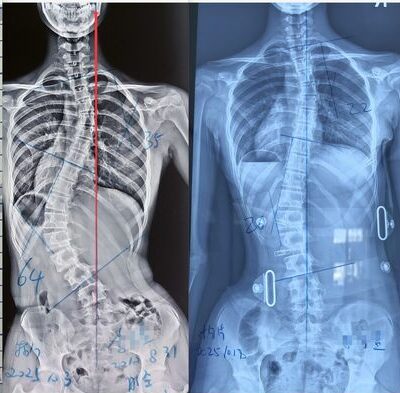

ما مدى سرعة تطور اعوجاج العمود الفقري؟ أسرع 3 مراحل زيادة للانحناء للأطفال والمراهقين يتساءل كثير من الأهل عند تشخيص ابنتهم أو ابنهم بـ اعوجاج العمود الفقري:هل سيزداد الانحناء بسرعة؟ كم يستغرق حتى يصبح

متى يصبح الوقت متأخرًا جدًا لعلاج الجنف بالعلاج الطبيعي؟ الإجابة لكل أب وأم عند تشخيص الطفل أو المراهق بالجنف (اعوجاج العمود الفقري)، يتكرر سؤال مهم لدى الأهل: هل ما زال هناك وقت للعلاج الطبيعي؟